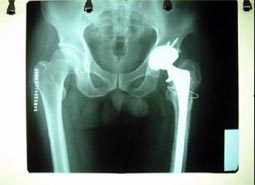

全髋置换术                                单纯股骨头置换术